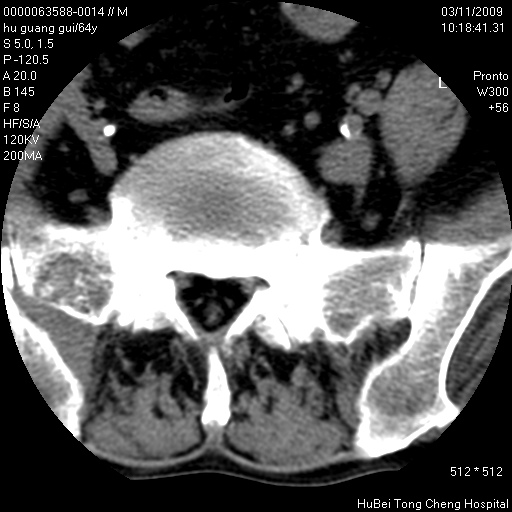

患者 男,64岁。腰痛十余天。(临床未提供其他病史)

临床诊断:腰痛原因待查(腰椎间盘突出症?)。

腰椎间盘ct轴位平扫(层厚5mm,层距4mm),图像如下:

腰椎退行性变,腰4—5椎间盘膨出。

右侧骶骨侧块骨侵蚀,骶髂关节骨性关节面破坏,并见软组织肿块,考虑骨转移瘤可能,进一步检查。

1.腰椎退行性变,腰4—5椎间盘膨出。

2.右侧骶骨侧块骨侵蚀,骶髂关节骨性关节面破坏,并见软组织肿块,考虑:脊索瘤,骨转移瘤可能,进一步检查。

1)腰椎退行性变,l4—5椎间盘膨出。2)骶骨右侧块骨转移瘤可能,3)水平骶椎。建议作一步检查。